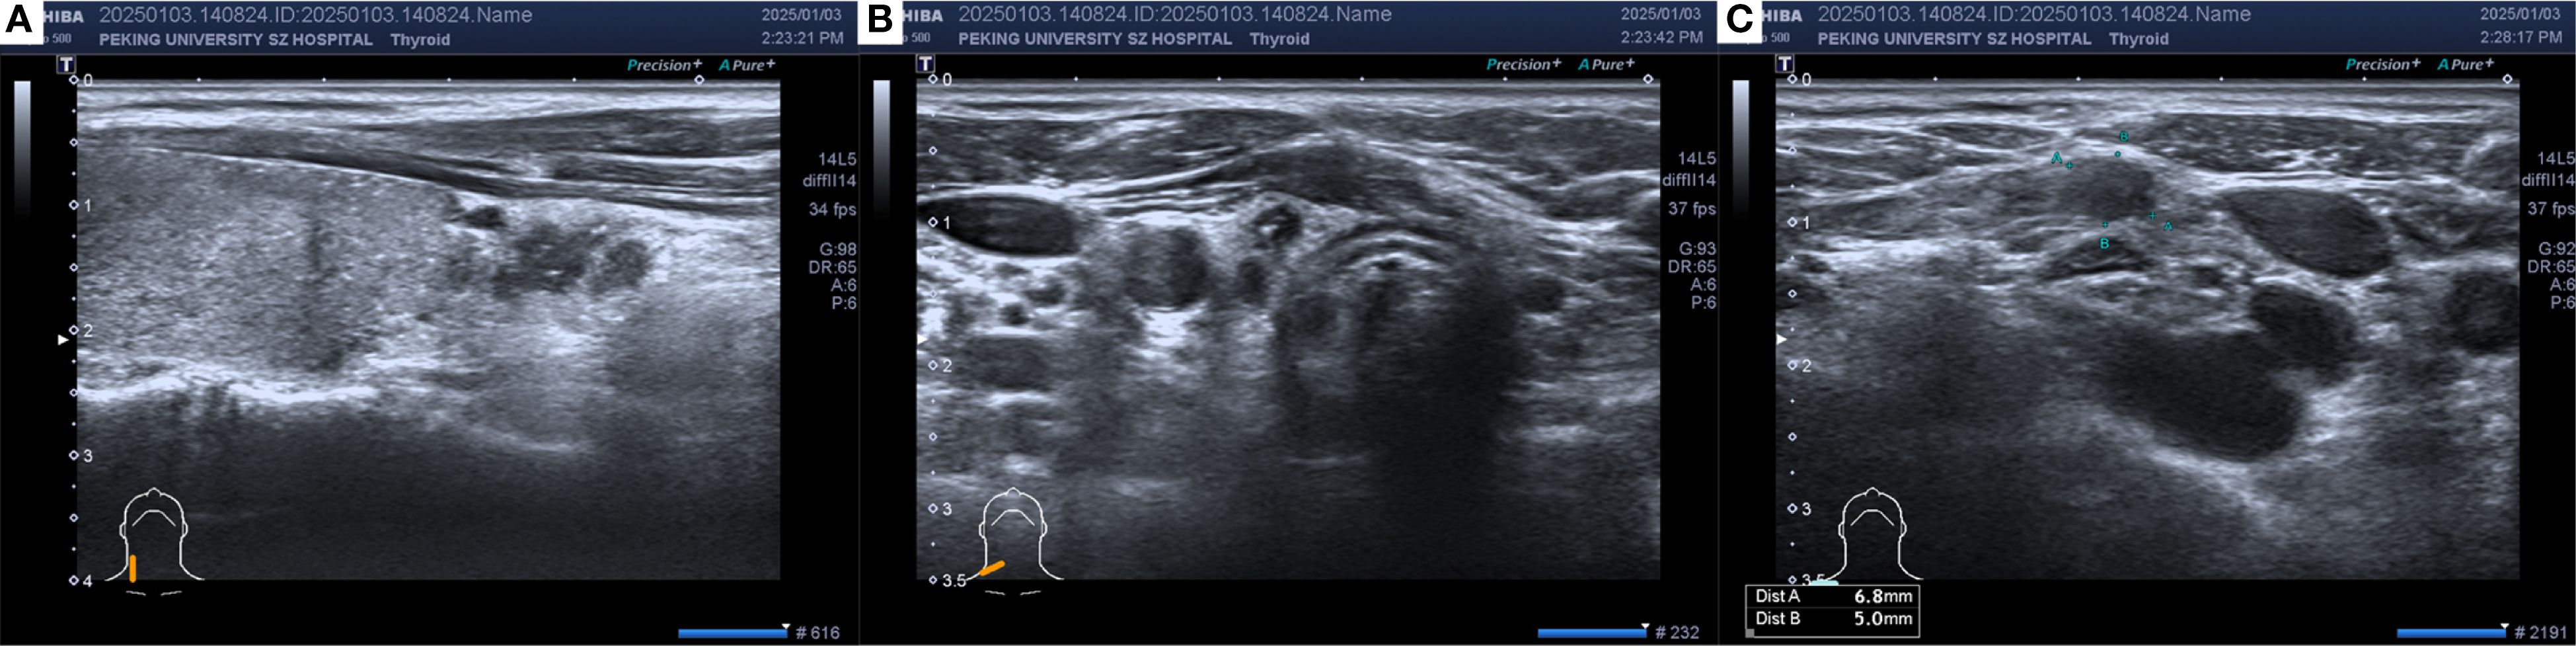

In December 2024, thyroid ultrasonography demonstrated diffuse parenchymal changes in the right lobe of the thyroid (Figure 1A), accompanied by multiple enlarged lymph nodes in the central and right lateral neck compartments (Figures 1B, C). A significant increase in the size of the nodule in the inferior pole of the right thyroid lobe was also noted (Figure 1A). Fine-needle aspiration biopsy (FNAB) of the nodule revealed features consistent with papillary thyroid carcinoma, with the possibility of a special histologic subtype. FNAB of the right lateral neck lymph node demonstrated findings suspicious for metastatic carcinoma, although the thyroglobulin (TG) level was undetectable (<0.1 ng/mL). Based on these results, the patient was diagnosed with papillary thyroid carcinoma of the right lobe with lateral lymph node involvement and subsequently underwent total thyroidectomy, bilateral central neck dissection (Level VI), and right radical neck dissection (Level II, III, IV and Vb). Postoperative pathology revealed that the right thyroid lobe was entirely replaced by a tumor, which was confirmed to be metastatic breast cancer (Figures 2A-C), with extensive lymphovascular invasion (Figure 2I) and lymph node metastases (8/8 in Level VI and 8/31 in Level II, IV and Vb, for a total 16/39). IHC demonstrated positivity for GATA3, ER (60%) and PR (2%), with HER2 negativity and a high proliferation index (Ki-67 70%) (Figures 2D-H), findings concordant with the patient’s previous diagnosis of Luminal B, HER2-negative breast cancer. The left thyroid lobe exhibited histological features of Hashimoto’s thyroiditis. Postoperative positron emission tomography/computed tomography (PET/CT) showed no evidence of distant visceral metastases, and serum tumor markers remained within normal reference ranges. The patient was advised to transition to an endocrine therapy regimen consisting of ovarian function suppression (OFS) with an aromatase inhibitor (AI) and a cyclin-dependent kinase 4/6 inhibitor (CDK4/6i), along with adjuvant radiotherapy to the right neck for metastatic breast cancer. Levothyroxine was also prescribed for thyroid hormone replacement. At present, the patient remains in stable condition with no evidence of recurrence or distant metastasis on serial surveillance imaging.

Figure 1. The thyroid ultrasound in December 2024: (A) Hypoechoic thyroid nodule located in the right thyroid lobe. (B) Enlarged lymph node in the central neck region (Level VI). (C) Enlarged lymph node in the right supraclavicular region. Heterogeneous echogenicity in the right thyroid lobe, with multiple scattered punctate hyperechoic foci. A hypoechoic nodule measuring approximately 13×4×8 mm with an irregular shape and punctate hyperechoic foci inside was observed in the lower part of the right lobe. Multiple hypoechoic nodules with irregular shapes, clear boundaries, cortical thickening, and loss of the lymph node hilum structure were found from level IV of the right neck to the right supraclavicular region, with a few hyperechoic foci inside.

Ultrasound remains the first-line imaging modality for thyroid diseases (20). However, distinguishing metastatic lesions from primary thyroid malignancies using ultrasound alone is challenging (4, 21). Thyroid metastases can be classified into two sonographic patterns: nodular and diffuse. The nodular type is characterized by single or multiple solid hypoechoic lesions with irregular margins and reduced vascularity (22, 23), whereas the diffuse type presents as a hypoechoic lesion involving the entire thyroid gland (22, 23). In the present case, ultrasound demonstrated heterogeneous echogenicity and diffusely scattered microcalcifications in the right lobe, findings consistent with reported cases (13, 21, 24).